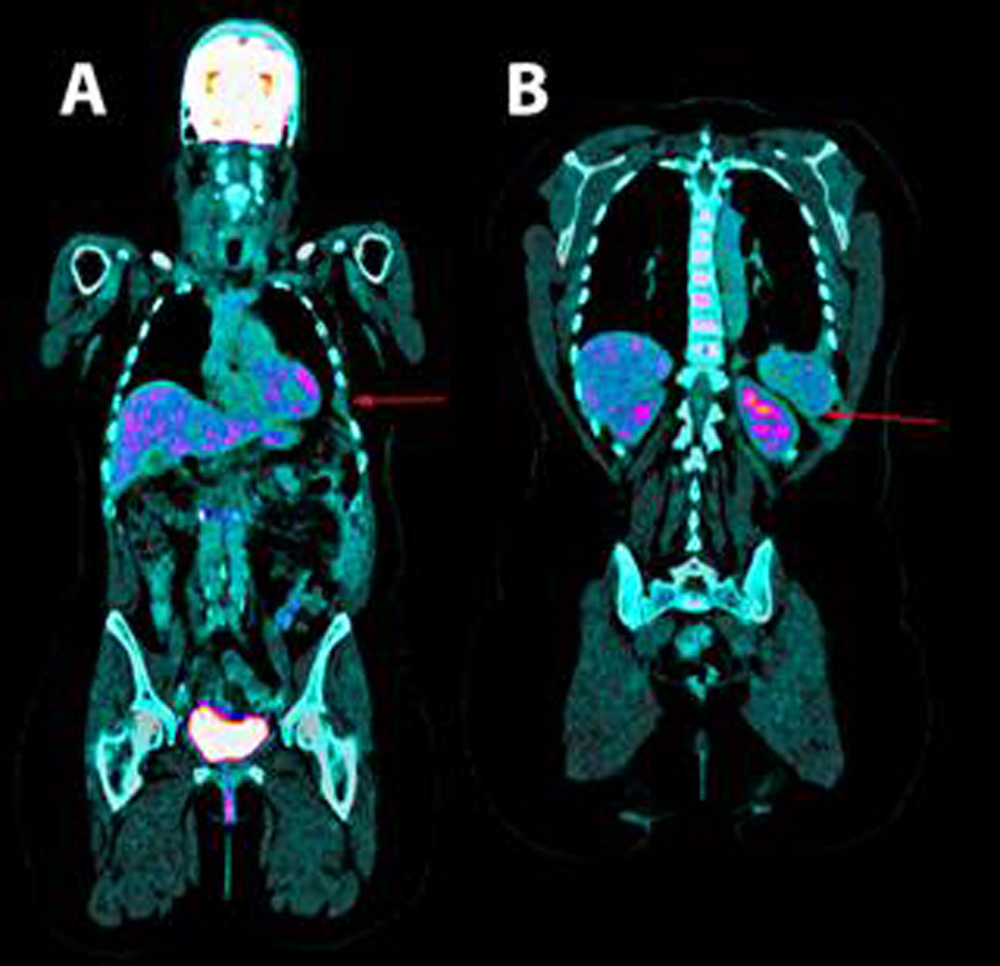

Se realizó una toracocentesis evacuadora con salida de líquido de características serohemáticas y que presentó los siguientes datos analíticos: glucosa 97 mg/dL, LDH 179 UI/L, hematíes 571,100/ μL, leucocitos 11,620/ μL (3% polimorfonucleares, 97% mononucleares), proteínas 5.3 g/dL, pH 7.43, factor reumatoide 9.1 UI/mL, amilasa 27 UI/L, colesterol 86 mg/dL, triglicéridos 26 mg/dL, adenosin desaminasa (ADA) 13 UI/L con citometría de flujo del líquido pleural negativa para infiltración linfoide y citología del líquido sin atipias celulares. Los cultivos en líquido pleural para bacterias, micobacterias, parásitos y hongos fueron negativos. Así mismo, la prueba del Mantoux y el test de detección del gamma-interferón mediante la prueba de quantiferon-TB® fueron negativas para infección tuberculosa latente. Las serologías para virus hepatotropos y virus de la inmunodeficiencia humana (VIH), fueron negativas. La mamografía y ecografía ginecológica fueron normales. Tanto en la gammagrafía ósea (Fig. 2) como en la tomografía computarizada, resonancia magnética torácica y tomografía por emisión de positrones (Fig. 3), se observó una hipoplasia y lesión osteolítica en el décimo y el sexto arco costal izquierdo, junto con un derrame, una importante inflamación pleural ipsilateral, y una afectación de partes blandas adyacentes.

Figura 3 Tomografía por emisión de positrones. A. se aprecia la ausencia del 6º y B. 10º arcos costales izquierdos.